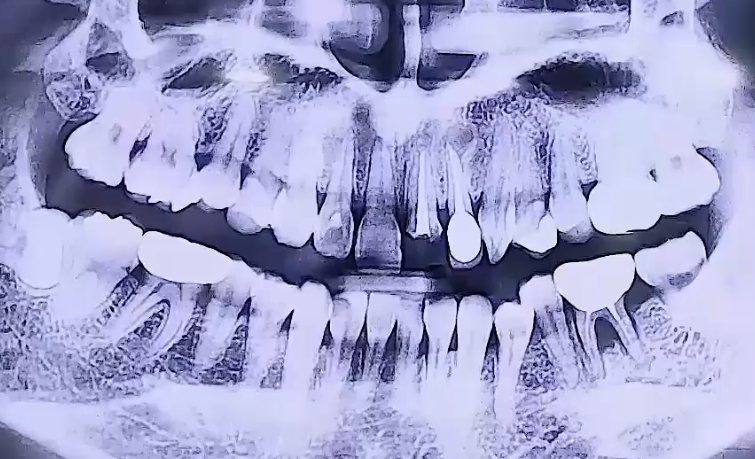

AFTER

왼쪽 아래 어금니 통증으로 내원해주신 환자분이십니다.

왼쪽 아래 뒤에서 두번째 큰 어금니를 타 치과에서 신경치료 후

보철치료까지 마무리하신 상태였는데, 그 주변 잇몸에 염증이 생기며

굉장히 부어 오르고 통증이 심했던 것으로 확인되었습니다.

해당 치아는 겉으로는 보이지 않는 잇몸 속에 염증이 생긴 것이기 때문에

잇몸치료를 해도 치아가 안 좋아질 가능성이 크므로 발치 후 임플란트를 결정하였습니다.

또한 위 앞니는 깨져있어서 기둥을 세우고 치아를 복원하는 보철치료를 진행하였어요.

오른쪽 아래 매복사랑니가 앞쪽 치아를 향해 옆으로 누워 아주 조금 나와 있어,

그쪽에 음식물이 끼면서 염증이 생길 수 있기 때문에 발치를 해드렸습니다.